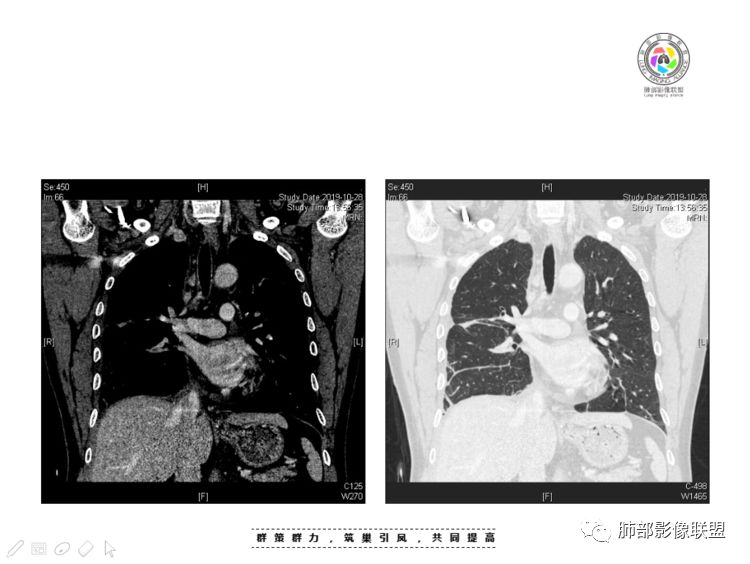

南边:大家看看前纵隔的病灶,符合肿瘤吗脂肪,周围密度增高

三个石头:比较散;像炎症的蔓延生长南边:是,这些看着心里不踏实觉得把这个纳入肿瘤去考虑是否合适总觉得边缘收缩的、散在的朝周围蔓延;中央还跨过脂肪,朝对侧胸膜蔓延把这个与囊性病变连到一起去考虑是否还需要斟酌一下因为这个就方向差异大了南边:连在一起,囊实性,边界不清,自然考虑恶性:如果独立,囊张力高、边界清楚,间隔,自然朝良性考虑:

我认为囊张力高,积液中的气体均在周围,外侧、下方,囊内有间隔:各腔密度不一致;提示:囊腔属于前纵隔,不是包裹性积液;现在的问题:囊腔与内侧的病灶是否是一体的

南边:我总觉得这个纵隔内不像是一个肿块的改变,扁平,周围蔓延:有符合炎性的的特点,或者肿瘤的侵犯;但是肿瘤的侵犯,不大符合,实性部位的边缘过于柔和,没有毛糙的侵犯边缘。

2、前纵隔内病灶囊实性混杂密度病灶,囊性病灶主要位于右侧,张力较高,有分隔影,囊壁右侧缘光整,病灶左侧实性部分边界不清明显强化,病灶肺瘤交界面大部分边界清楚,部分模糊。

纵隔内病灶不符合肺癌转移途径,且纵隔内单发的囊实性转移罕见。淋巴瘤无论是分布、形态、密度、还是强化方式度不符合。

患者缺乏纵隔炎的临床表现,囊性病损更难以解释。